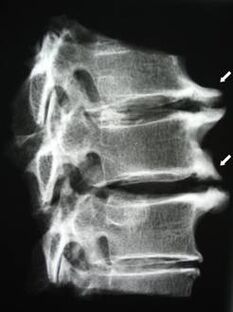

In the early stages, osteochondrosis is detected using MRI.Then, the pathology can be diagnosed using radiography.On radiographs of the cervical spine, a decrease in the distance between the vertebrae, pathological changes in the facet joints, and osteophytosis become apparent.

| Cervical osteochondrosis | The appearance of pathological changes in one or more segments of spinal motion.Impaired spinal mobility, development of myofascial pain syndrome and spinal root pinching | Pain, paresthesia and motor disturbances in the cervical region, which spread to the back of the head and upper limbs.Detection of characteristic changes in the spine on MRI and radiography (osteophytes, decreased distance between vertebrae, signs of damage to intervertebral joints) |